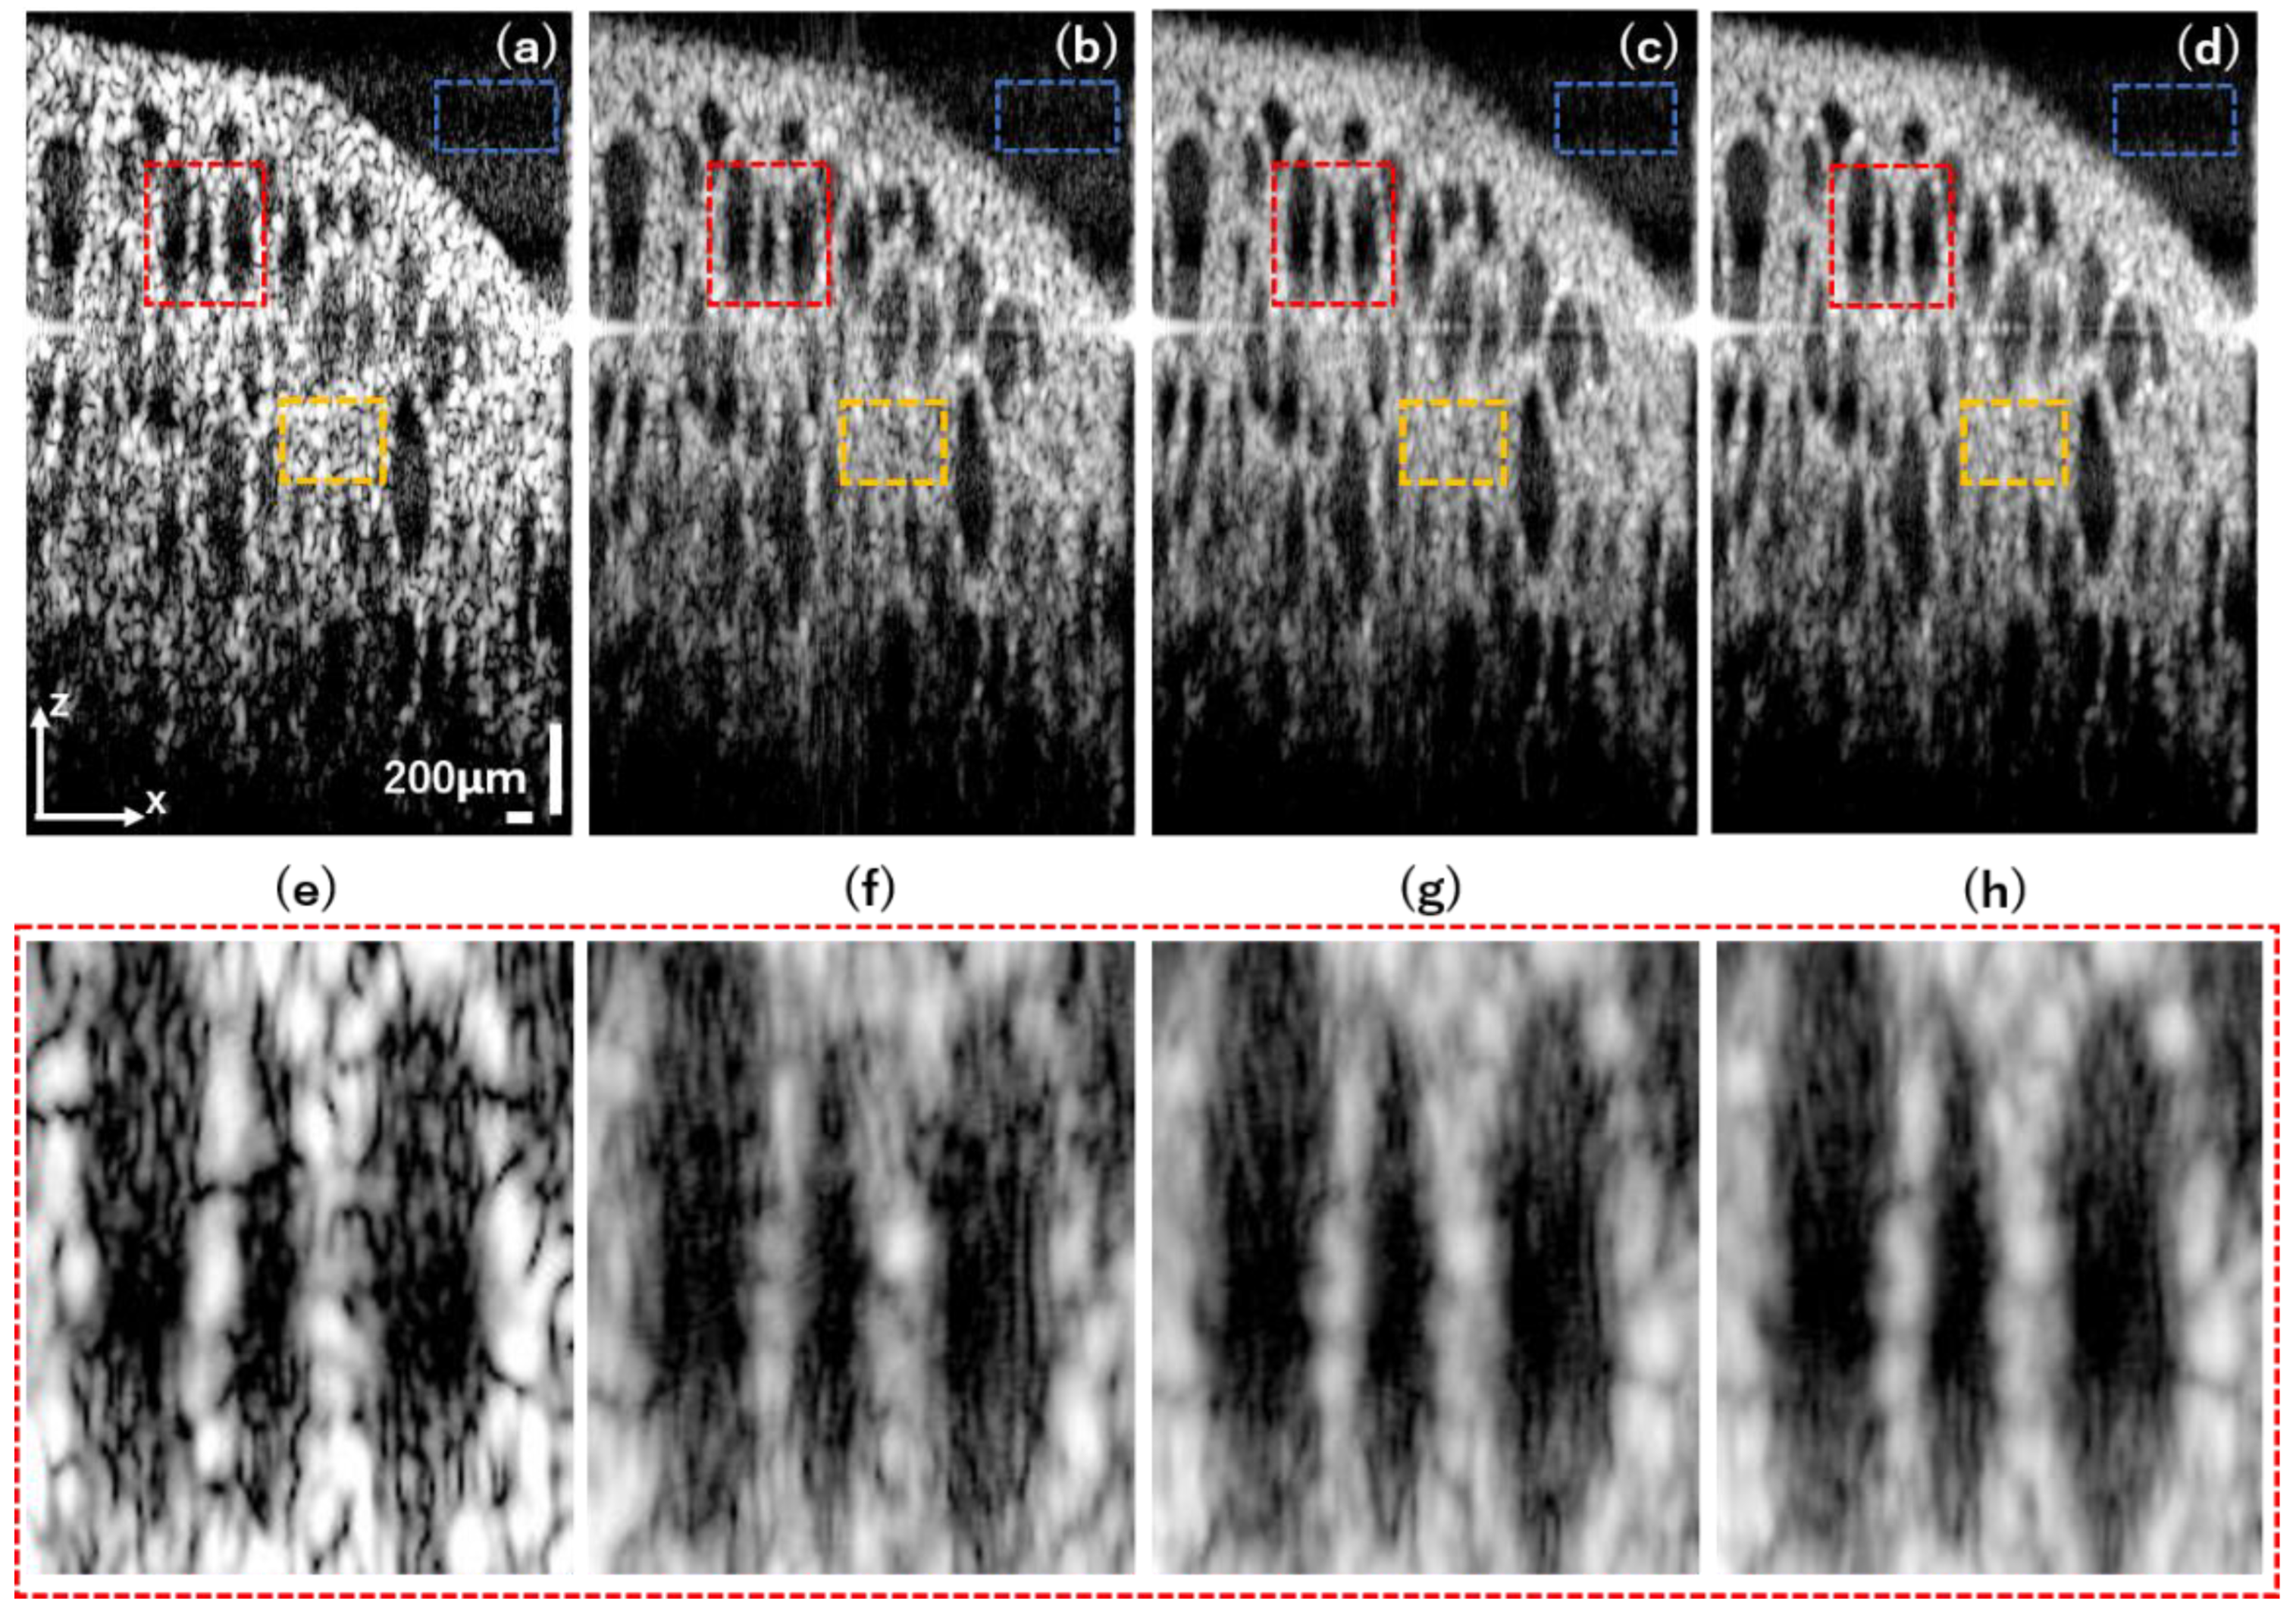

3.3. Pig Thyroid Gland

| SNR (dB) | 3.25 | 2.93 | 2.83 | 2.61 | 2.45 | 1.25 | 1.06 | 4.01 | 4.99 | 5.24 |

| C | 18.53 | 20.64 | 21.50 | 20.43 | 19.48 | 5.51 | 4.67 | 21.11 | 30.74 | 41.90 |

| CNR (dB) | 3.11 | 2.89 | 2.80 | 2.59 | 2.30 | 0.80 | 0.62 | 3.96 | 4.99 | 5.24 |

| Imaging depth (mm) | 1.31 | 1.44 | 1.45 | 1.54 | 1.46 | 1.40 | 1.14 | 1.70 | 1.82 | 1.82 |